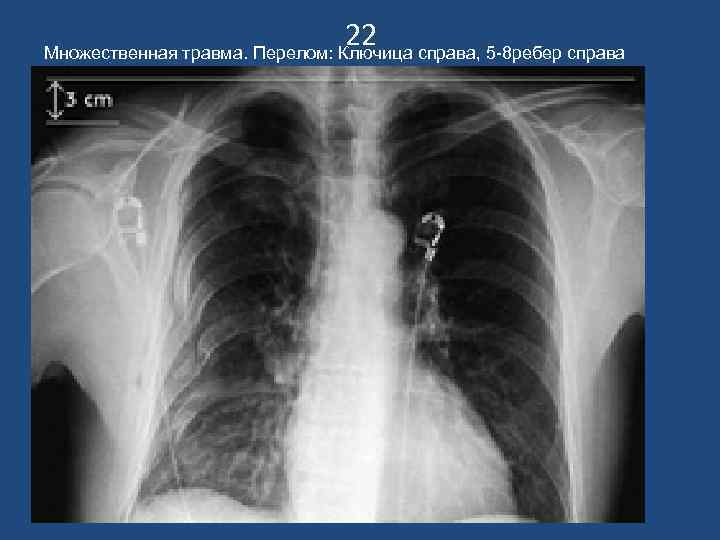

22 Множественная травма. Перелом: Ключица справа, 5 -8 ребер справа